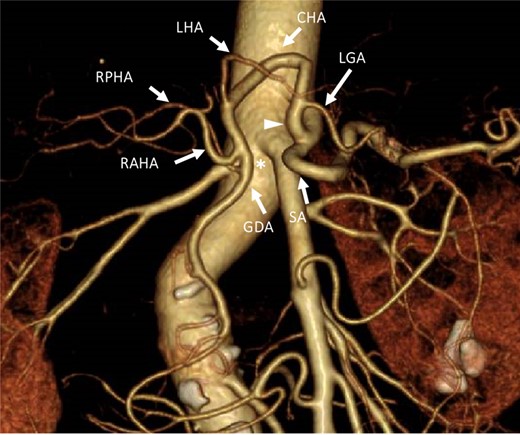

A 67-year-old woman with a 1-month history of epigastric pain was referred to our hospital with suspected pancreatic head cancer. Endoscopic ultrasonography and fine-needle biopsy of the tumor revealed adenocarcinoma of the pancreatic head. Computed tomography (CT) showed a 17 × 12 mm hypovascular tumor without arterial or portal venous invasion in the pancreatic head, and the CHA formed a common trunk with the LGA, coursing within the lesser omentum (Fig. 1). In addition, preoperative three-dimensional CT angiography revealed that the celiac artery branched into the splenic artery and the common trunk, and the usual CHA was absent in the supra-pancreatic area. The CHA formed a common trunk with the LGA and arched in a cranial direction within the lesser omentum immediately adjacent to the liver. No other arterial supply to the liver was identified (Fig. 2). With the preoperative diagnosis of resectable pancreatic head cancer and clinical staging of T2N0M0 (UICC 8th edition), pancreatoduodenectomy was planned.

Three-dimensional computed tomography angiographic image from an anteroposterior view. The celiac artery branched into the SA. A common trunk (white arrowhead) branched into the LGA and the common hepatic artery, which arched toward the cranial side. No arterial bridge existed between the celiac trunk and the GDA (asterisk). LGA: left gastric artery. CHA: common hepatic artery. SA: splenic artery. LHA: left hepatic artery. RAHA: right anterior hepatic artery. RPHA: right posterior hepatic artery. GDA: gastroduodenal artery.